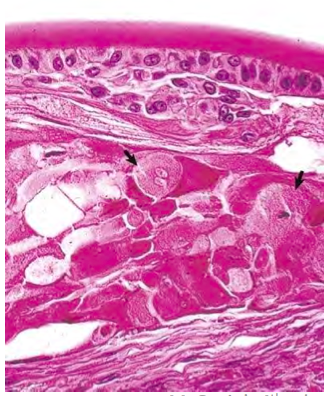

Corneal edema due to an ulcer

Ulcer stains green with flourescein dye